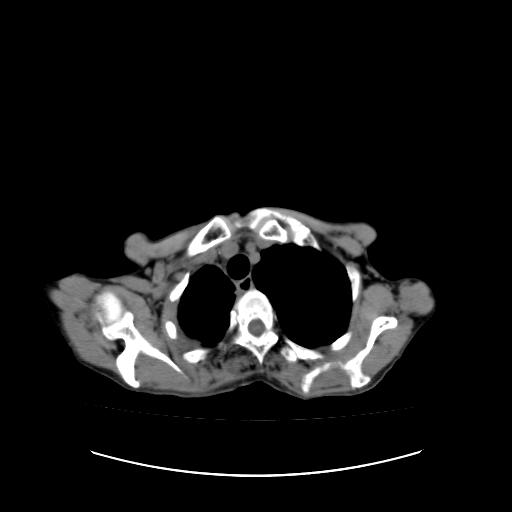

右侧胸膜增厚,局部呈结节状增厚,右侧胸腔少量积液。双肺未见确切肿块影。纵隔未见淋巴结肿大。气管、支气管通畅。考虑右侧胸膜间皮瘤(恶性?)可能性大。不除外癌性胸膜炎。

右侧胸廓塌陷,右侧胸膜广泛增厚并见多发胸膜结节,右侧少量胸腔积液并包裹。

右侧广泛胸膜增厚,局部呈结节状增厚,右侧胸腔少量积液。双肺未见确切肿块影。纵隔未见淋巴结肿大。气管、支气管通畅。考虑右侧胸膜间皮瘤(恶性?)可能性大。支持!